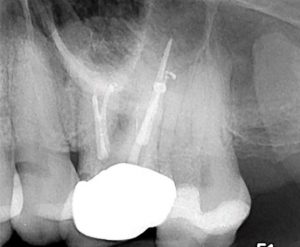

After debridement and shaping, Ca(OH)2 (Ultrocal XS) was placed in the root canal space to further enhance disinfection. Prior to obturation, drainage was noted coming from the MB2 canal; drainage was arrested and the canals root was filled with vertical condensation of warm gutta percha (VCWG) and AH-Plus sealer (Figure 3)